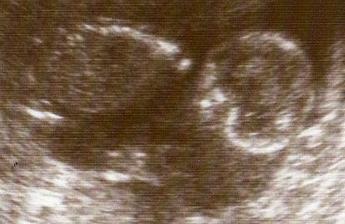

20.1.09-velký UTZ,vše je v pořádku.Nejeví se žádné známky postižení.

28.1.09-Výsledky z plodové vody jsou v pořádku,jsme ZDRAVÍÍÍ!A na 100% čekáme chlapečka!